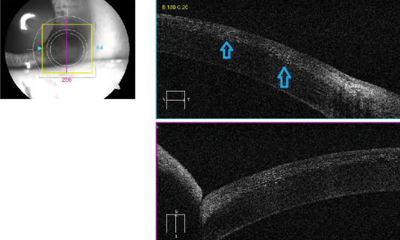

Anterior segment OCT showed diffuse hyper-reflective dots in the flap-stromal interface (Figure 3). A clinical diagnosis of diffuse lamellar keratitis was made.

Figure 3: Anterior segment OCT showed diffuse hyper-reflective dots in the flap-stromal interface.